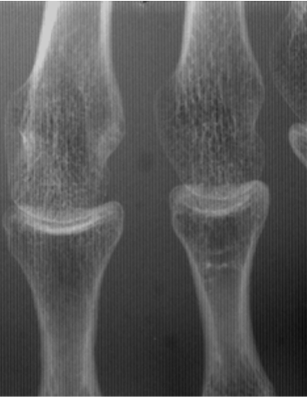

グリッド無し

ピクセル・アラインド・グリッド

一般的なグリッド

通常グリッド+グリッド目除去処理